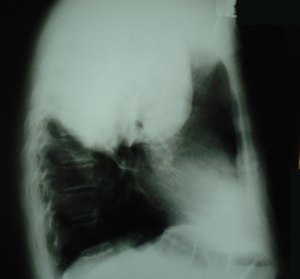

Εικόνα 2

Πλάγια ακτινογραφία θώρακος, ευμεγέθης μάζα στο οπίσθιο-μέσο-άνω πνευμονικό πεδίο, με ομοιογενή σύσταση και ομαλά όρια.